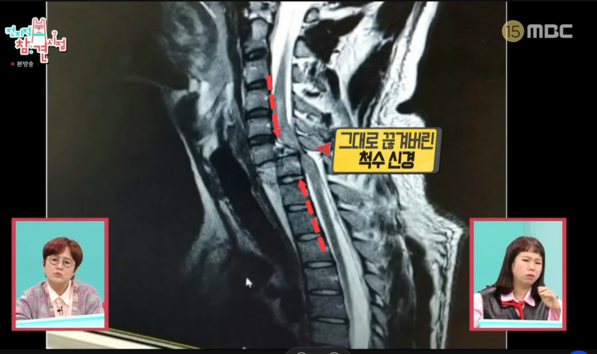

낙상사고로 인해 박위는 목이 부러지면서 경추 골절과 척수 신경 손상을 겪었습니다. 이러한 부상은 그의 신체 기능에 심각한 영향을 미쳤고, 결국 전신마비 진단을 받게 되었습니다.

- 척수 신경 손상: 경추 손상은 신경계를 손상시키는 가장 치명적인 부상 중 하나입니다. 박위는 이 사고로 인해 하반신은 물론 상체의 움직임도 불가능한 상태에 놓였습니다.

- 사고 발생 경위: 파티 중 박위는 술에 취해 필름이 끊겼고, 그 상태에서 건물과 건물 사이에서 추락하게 되었습니다. 4미터 높이에서 떨어지며 목이 부러지고, 척수 신경이 손상되면서 전신마비를 얻게 되었습니다.